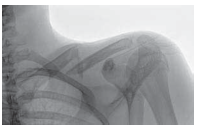

Plate Fixation of Clavicle Fractures DEFINITION ■ Displaced, comminuted fractures of the clavicle are at …

clavicle fracture Anatomy of clavicle The clavicle is the bone that connects the breastplate (sternum) to the…